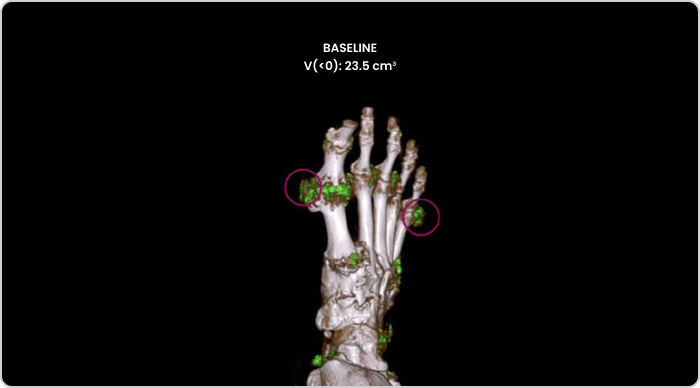

Dual Energy CT scan of uric acid buildup in foot at baseline

MIRROR RCT AT BASELINE

DECT image of urate buildup from a patient in MIRROR RCT.2

DECT, dual-energy computed tomography.

The primary endpoint in MIRROR RCT was defined as the proportion of patients achieving and maintaining an sUA level of <6 mg/dL for at least 80% of the time during Month 6; 71% of patients receiving KRYSTEXXA with methotrexate (n=100) vs 39% of patients receiving KRYSTEXXA alone (n=52) met the primary endpoint (P<0.0001).3

Tophi resolution was a secondary endpoint that was defined as 100% resolution of at least one target tophus, no new tophi appearing, and no single tophus showing progression at Month 12; 54% (28/52) of patients receiving KRYSTEXXA with methotrexate achieved tophi resolution vs 31% (9/29) of patients receiving KRYSTEXXA alone (P=0.048).3,4